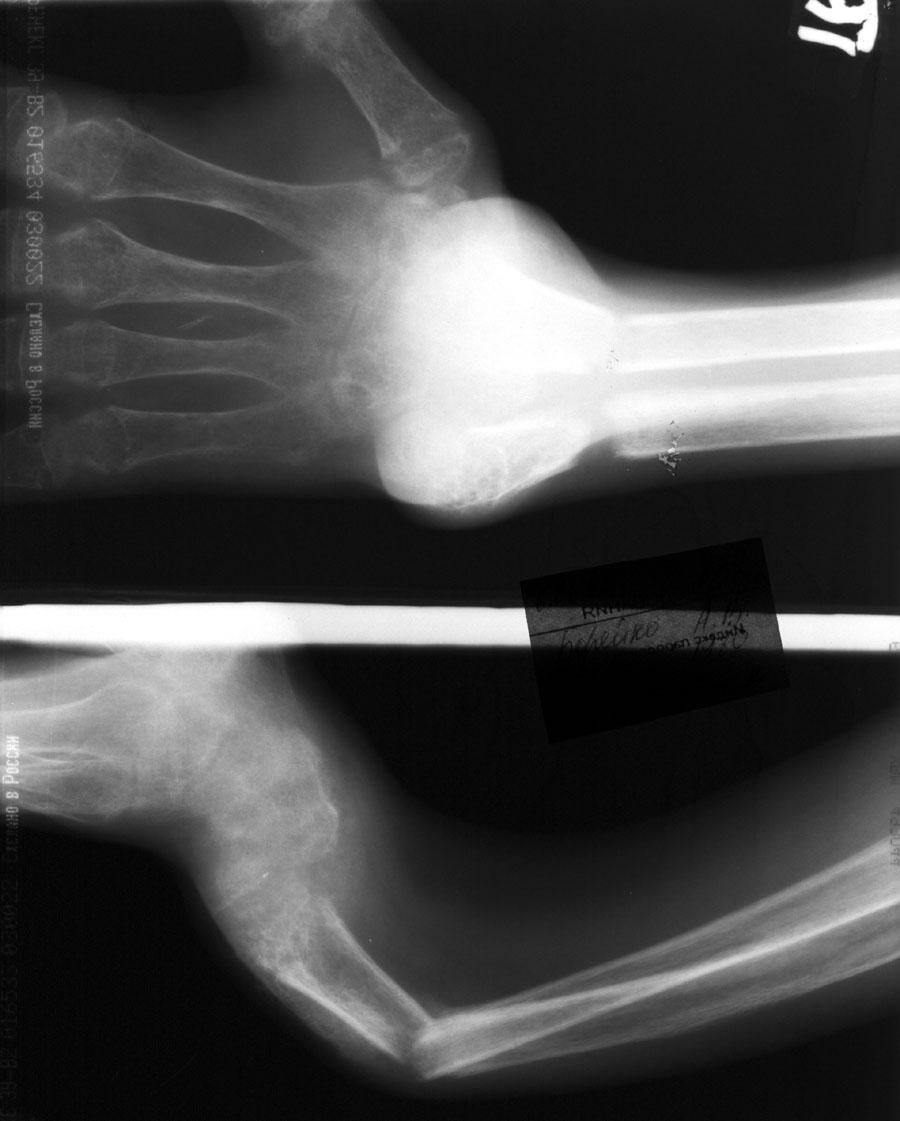

Выписка из амбулаторной карты пациента, 1980 г.р.Находится под наблюдением в поликлинике КНЦ РАН. Состоит на "Д" учёте по заболеваниям:Ювенильный идиопатический генерализованный остеопороз. Деформация грудной клетки за счёт множественных переломов грудины, рёбер. S-образный кифосколиоз грудного отдела позвоночника.Синдром гипофосфатемии неясного генеза. ВСД по кардиальному типу.Инвалид 1-й группы с детства. Последние 4 года не может передвигаться, возникают патологические переломы. Живёт в семье, материально-бытовые условия удовлетворительные.За последние 2 года состояние значительно ухудшилось - усилилась общая слабость, участились патологические переломы, которые не срастаются. Постоянно лежит в постели. Постоянный приём препаратов кальция и диеты с повышенным содержанием кальция, фосфора и белка эффекта не дают. С 11.07.2002 по 30.07.2002 г. лечился в травматологическом отделении АЦГБ с переломом костей правого предплечья со смещением. С 24.08.2002 по 08.09.2002 г. лечился в терапевтическом отделении по поводу острого бронхита с бронхоспастическим компонентом.На сегодняшний день статус. Состояние относительно удовлетворительное. В сознании. Положение вынужденное: сидя в инвалидном кресле, сам встать на ноги и передвигаться не может, туалет только с помощью родственников. Бледный, астеничный. Выраженная деформация грудной клетки, выраженный кифоз и сколиоз грудного отдела позвоночника. Экскурсия грудной клетки ограничена. Участие в акте дыхания вспомогательных межрёберных мышц. Пальпация грудной клетки безболезненна. Деформация всех крупных и мелких суставов за счёт увеличенных эпифизов. Деформация длинных трубчатых костей, мышцы рук и ног атрофичны. Температура - 36,8, ЧД - 29 в минуту. Дыхание жёсткое, проводится во все отделы. Слева от угла лопатки и в аксиллярной области влажные мелкопузырчатые хрипы, в межлопаточной области с обеих сторон свистящие хрипы. Пульс 90 ударов в минуту, ритмичный, симмитричный, слабого наполнения и напряжения. АД 120\80 мм рт. ст. Границы относительной сердечной тупости не расширены. Тоны сердца громкие, ритм правильный. Язык влажный, блестит. Живот при пальпации мягкий, не вздут, симметричный, участвует в акте дыхания, безболезненный. Печень по краю рёберной дуги. Стул регулярный, оформлен, без патологических примесей. Мочеиспускание свободное, безболезненное. Симптом Пастернацкого отрицателен с обеих сторон. Отёков нет.Анализ крови общий 26.08.2002: Hb-146 г\л, Эр.-4,8, ЦП-0,91, Лейк.-6,4, п.-4, с.-45, э.-5, м.-11, СОЭ-4 мм\ч.Анализ мочи общий 26.08.2002: Уд. вес-1025, белок-0,01, сахар-нет, лейк.-0-1 в поле зр., слизь+++, бактерии+.Анализ крови биохимический 26.08.2002: глюкоза-4,9, АЛТ-0,3, АСТ-0,5, биллирубин-11,9, креатинин-44,2, мочевина-3,8, СРБ (+).Анализ крови на микрореакцию - отрицательный.Флюрограмма за 2002: Резко выраженная деформация грудной клетки за счёт множественных переломов рёбер, грудины. Инфильтративных теней в лёгких не определяется. По сравнению с предыдущим исследованием от 01.12.2000 г. - ухудшение: нарастают деформация грудной клетки и позвоночника.ЭКГ за 2002 год: Синусовая тахикардия с ЧСС 88 в минуту. Отклонение ЭОС вправо. Признаки нарушения процессов реполяризации миокарда задней стенки левого желудочка. Повидимому, изменения ЭКГ обусловлены позиционными изменениями, возможно астеничным телосложением.Дополнительные методы исследования.Рентген правого предплечья (17.10.2002): Металлоостеосинтез по поводу перелома обеих костей правого предплечья в н\з: признаки репарации практически не определяются, сохраняется диастаз между отломками.Рентген правого предплечья (24.04.2003): Металлоостеосинтез по поводу перелома обеих костей правого предплечья в н\з: признаки репарации отсутствуют, формируются ложные суставы. Резко выраженный остеопороз.Рентген правого бедра (18.02.2003): Несросшийся перелом правого бедра на границе с\з и н\з со смещением отломков под углом открытым кнутри. Формирующийся ложный сустав. Выраженный остеопороз костей.Рентген правого бедра (24.04.2003): Угловое смещение отломков правого бедра увеличилось. Признаки репарации крайне вялые: по наружному краю отломков формируются замыкательные пластинки - ложный сустав. Выраженный остеопороз.